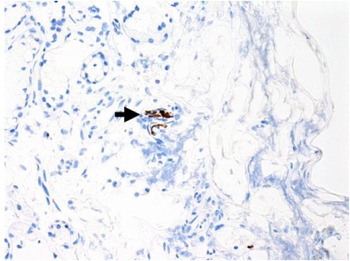

Immunohistochemical staining for pan-cytokeratin AE1/AE3 antibodies demonstrated only very focal residual attenuated surface epithelium (Figure 4). There was strong nuclear and cytoplasmic positivity for S100 immunostain in scattered cells within structures, compatible with Bowman's glands (Figure 5); the same immunostain highlighted small nerve bundles, possibly of trigeminal origin. Immunostaining for angiotensin-converting enzyme 2 (ACE2) receptor showed focal membrane staining in the S100 positive cells in Bowman's glands (Figure 6). There was focal positive staining for synaptophysin, and neurofilament immunostain highlighted small neurites and nerve bundles in lamina propria (Figure 7). No abnormal neural proliferation was identified.

Fig. 6. Immunostaining for angiotensin-converting enzyme 2 (ACE2) receptor showed focal membrane staining in cells that were also positive for S100 in Bowman's glands (arrow). (ACE2 immunostain; ×200)

Fig. 7. Focal positive staining for neurofilament immunostain highlighted small neurites and nerve bundles in lamina propria (arrow). (Neurofilament immunostain; ×100)

The ACE2 receptor is considered the portal of entry for SARS-CoV-2, and upregulation of ACE2 receptors may increase the risk of infection.Reference Hoffmann, Kleine-Weber, Schroeder, Kruger, Herrler and Erichsen29 No upregulation was detected in our patient's biopsy.